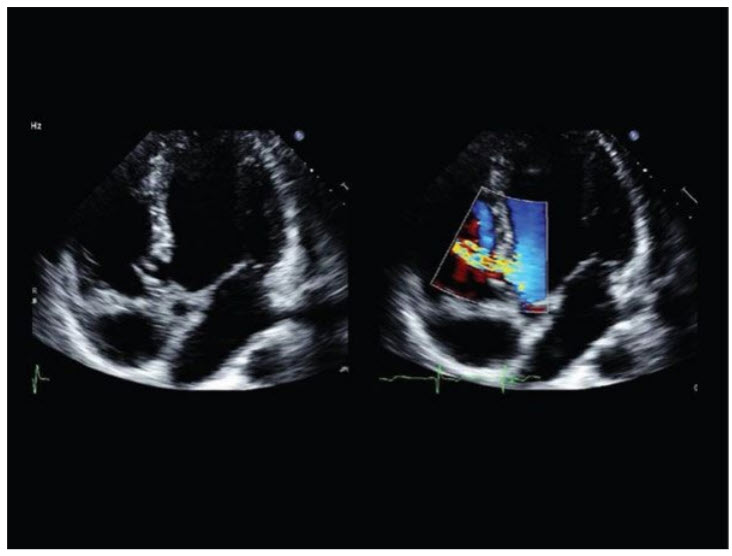

Review the image taken at the time of percutaneous closure of an intracardiac shunt in a 25-year-old patient (Fig. below).

Which of the following defects was closed in this patient?

Secundum ASD. The majority of secundum ASDs can be closed with a percutaneous catheter technique. ASD closure is indicated for RA and RV enlargement with or without symptoms. Small ASDs (<5 mm) with no evidence of volume overload do not require closure unless associated with cryptogenic paradoxical embolism. Sinus venous, coronary sinus, and primum defects are not amenable to device closure (Fig. below).